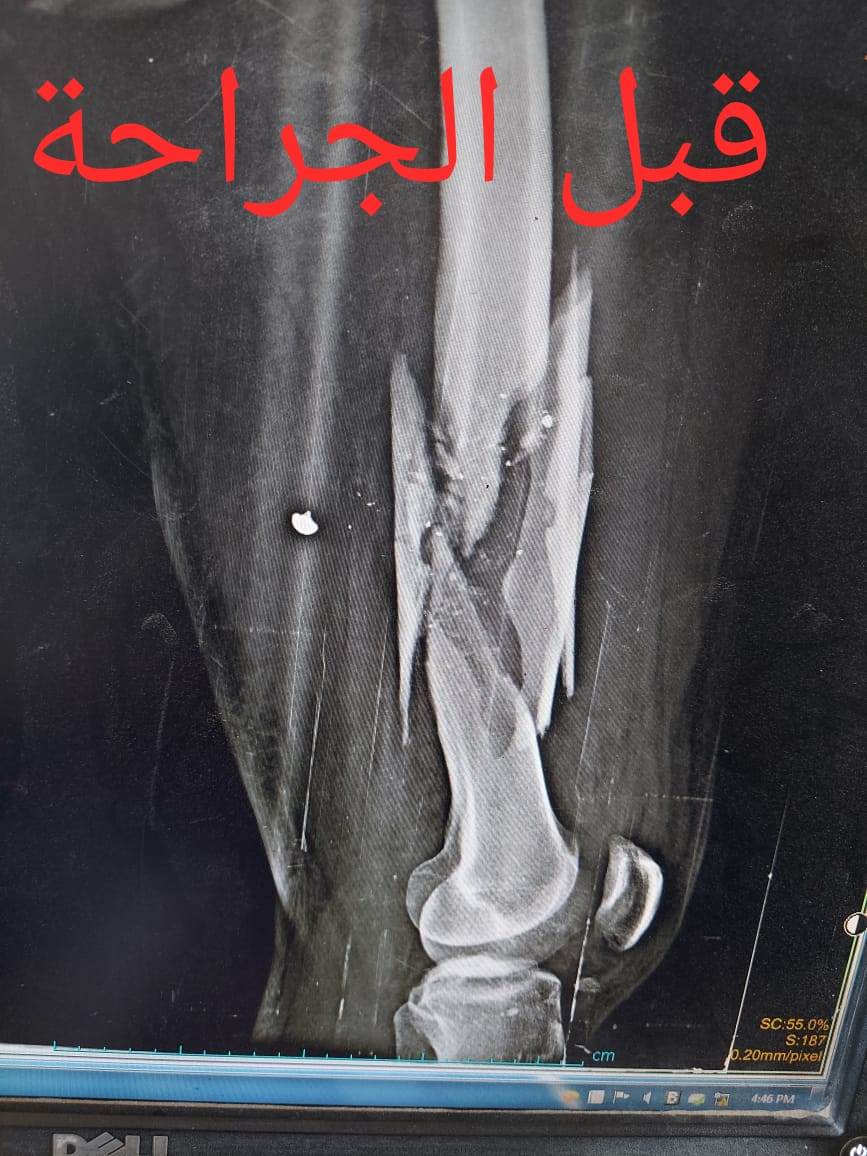

أعلن الدكتور سعد مكي، وكيل وزارة الصحة بالدقهلية، نجاح فريق طبي بمستشفى شربين المركزي، في إنقاذ شاب مصاب بكسر متفتت بالفخذ إثر بطلق ناري.

حيث تم إجراء تدخل جراحي دقيق لشاب يعاني من كسر مضاعف من الدرجة الثالثة، إثر طلق ناري، أدى إلى تهتك بالأنسجة، وكسور متفتتة بالفخذ، وذلك عن طريق جهاز "الليزاروف"، وتعد واحدة من عمليات العظام الكبرى والمتقدمة ذات المهارة الخاصة.